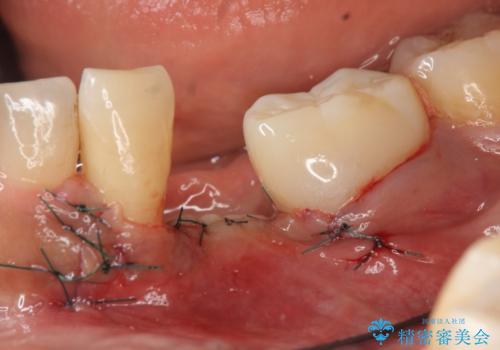

歯列矯正は御希望されなかったため左下4、5番目の歯を抜歯し、インプラントによる欠損補綴を行いました。

左下6も再根管治療後、オールセラミッククラウンによる補綴を行いました。

今回用いたオールセラミッククラウンはジルコニアフレームという白い素材の上にセラミックを盛っているため、審美性が非常に高いのが特徴です。

また、ジルコニアは人工ダイヤモンドの材料にも使われているほど高い強度を持っており、そのためオールセラミッククラウンは審美性だけでなく、奥歯やブリッジの補綴も可能とするクラウンです。